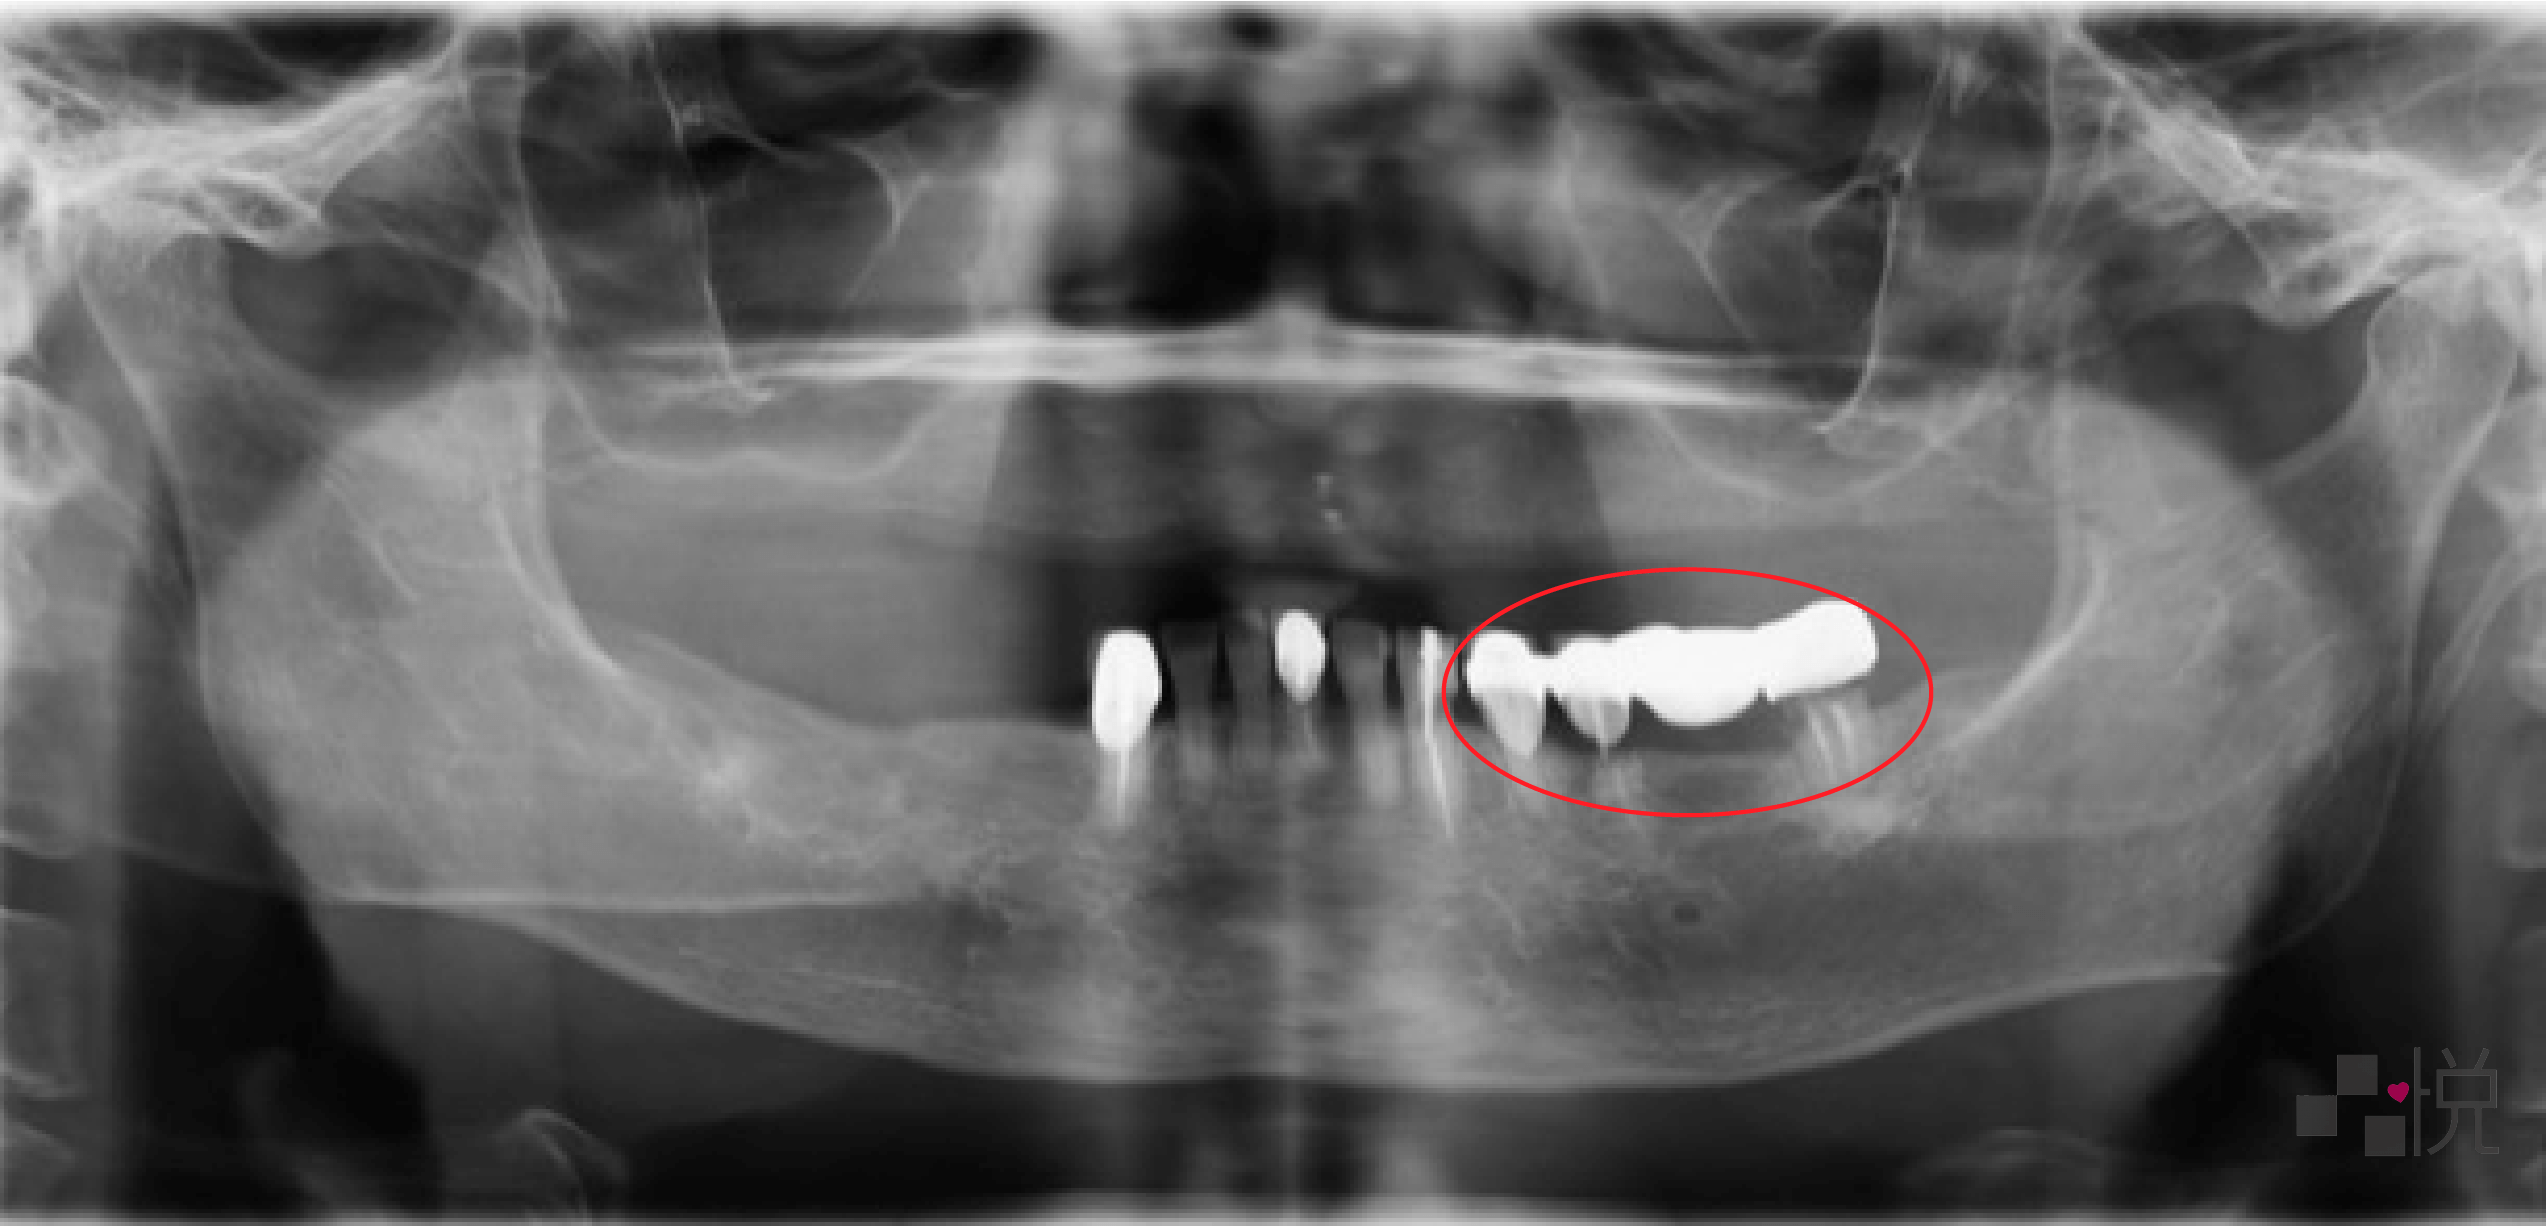

由於長期發炎造成骨頭都被侵蝕,外觀嚴重塌陷,缺牙區採用兩階段補骨及植牙。

同場加映:當天拔牙就植牙!搭配X-Guide藍光3D導航植牙機的優勢

中間過程怕會沒有門牙、不但不美觀且無法進食,因此使用臨時活動假牙,大大提升過程中的生活品質。

由於本來的缺損太嚴重,最終假牙部分則採用陶瓷假牙肉來模擬真牙,並搭配多種不同的假牙形式,歷時一年多,終於重建進食功能及笑容,讓全院所的醫護都相當欣慰。